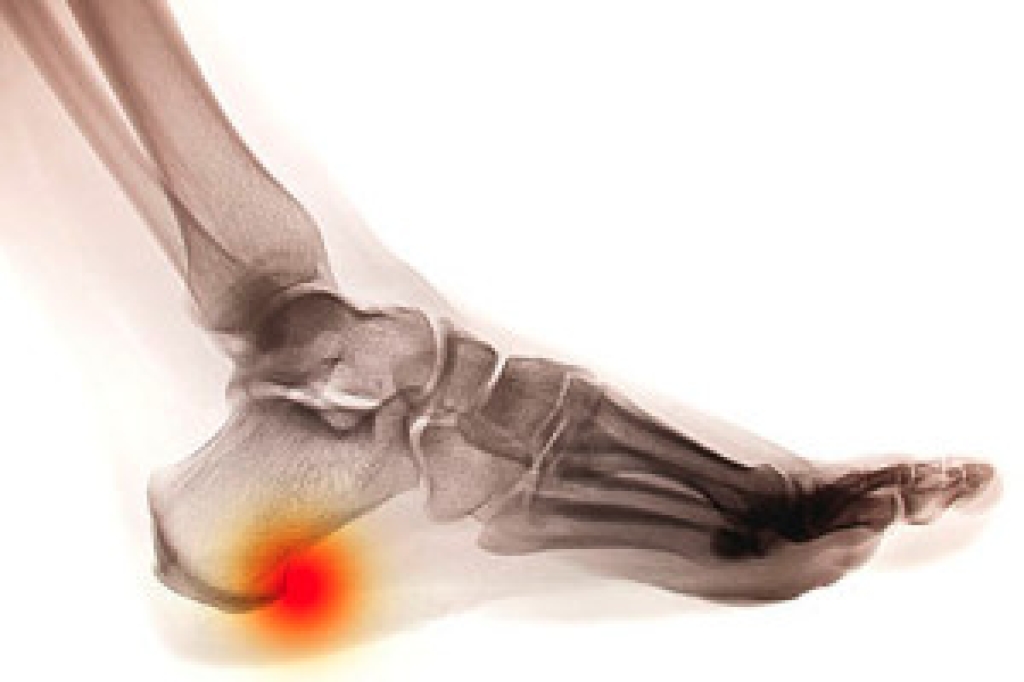

Sever’s disease is also known as calcaneal apophysitis, which is a medical condition that causes heel pain I none or both feet. The disease is known to affect children between the ages of 8 and 14.

Sever’s disease occurs when part of the child’s heel known as the growth plate (calcaneal epiphysis) is attached to the Achilles tendon. This area can suffer injury when the muscles and tendons of the growing foot do not keep pace with bone growth. Therefore, the constant pain which one experiences at the back of the heel will make the child unable to put any weight on the heel. The child is then forced to walk on their toes.